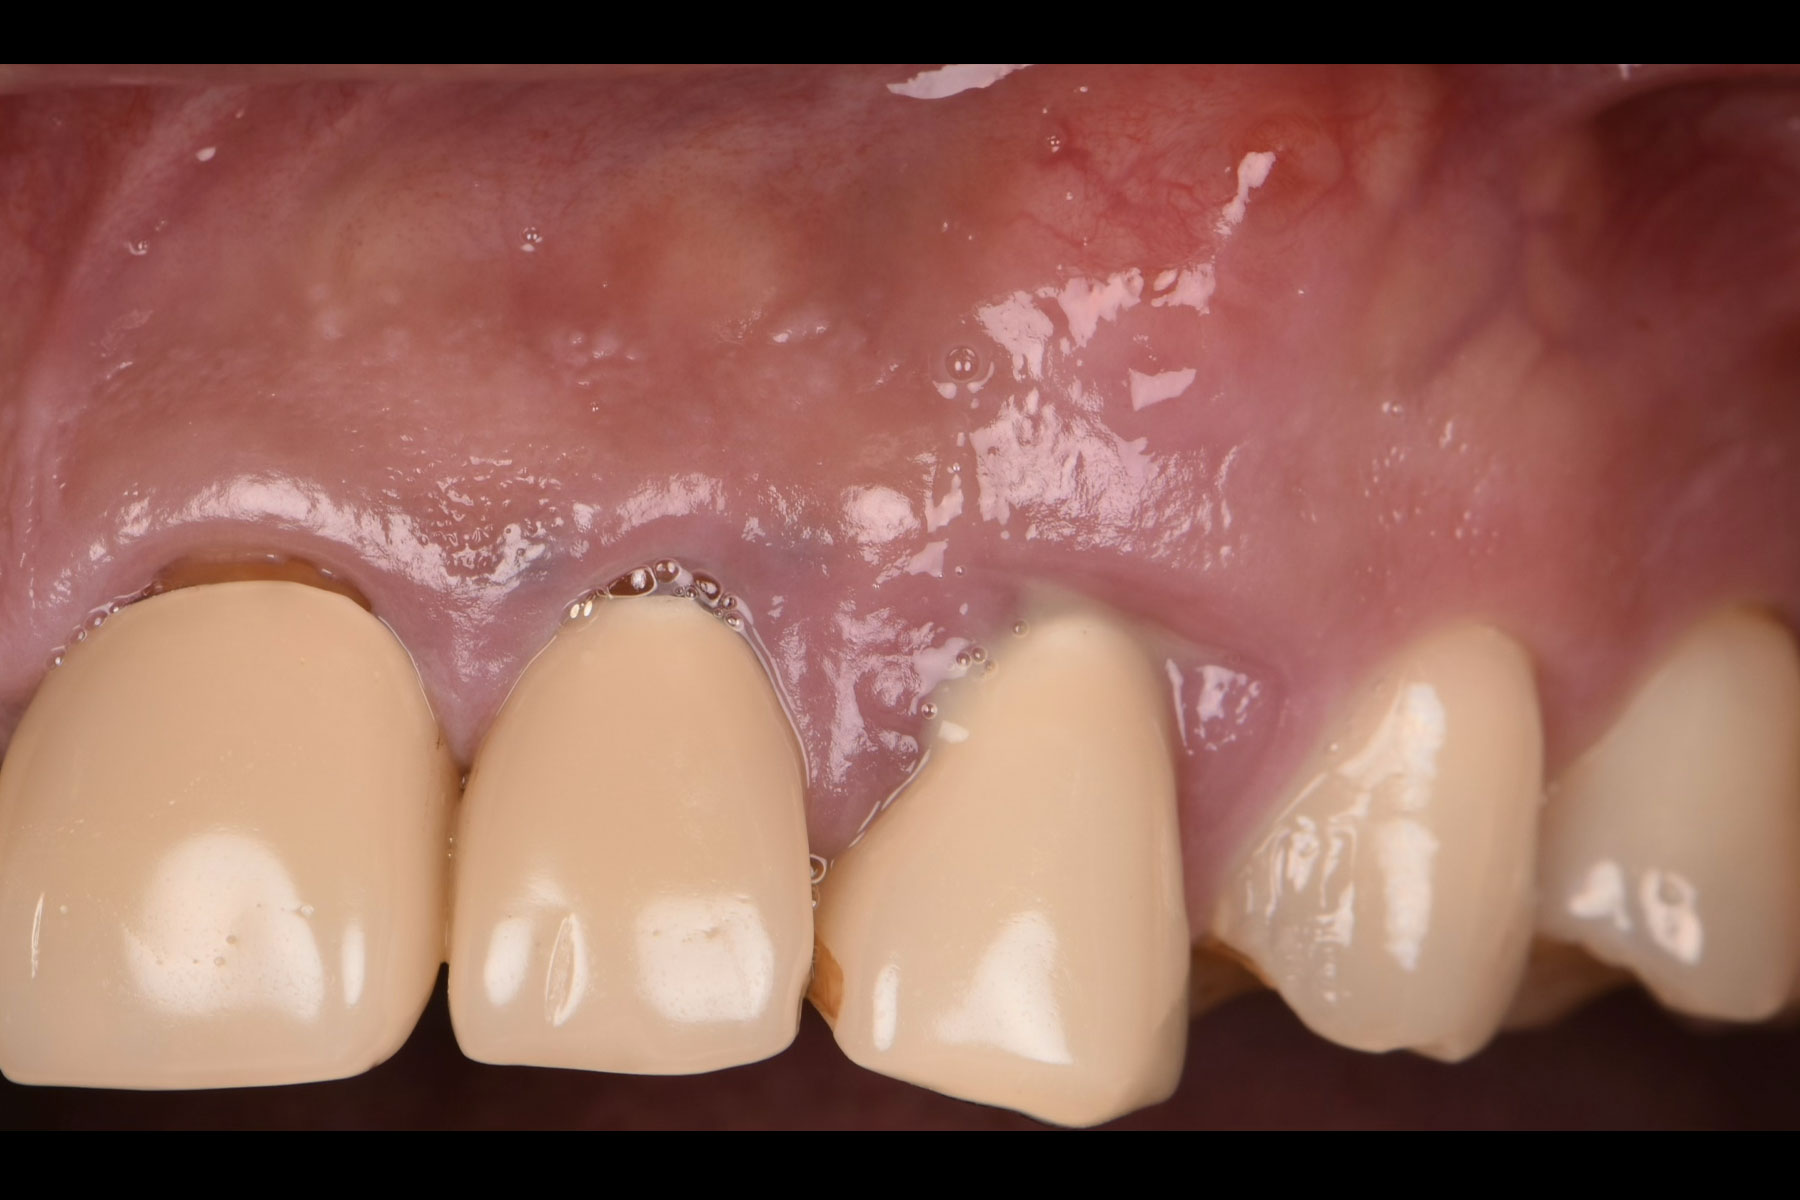

治療後